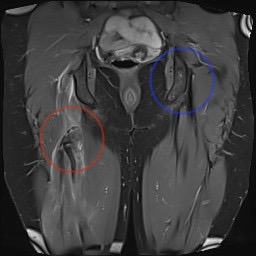

Proximal hamstring tear on right (red circle), normal insertion on tuberosity on left (blue circle)